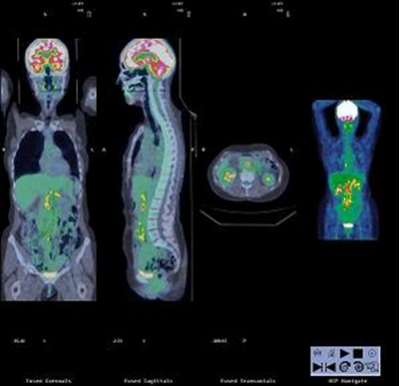

Le PET Scan comme son nom l’indique combine la TEP et le scanner. Il s’git d’une technologie très récente et apparait comme un outil fondamental de dépistage et de suivi du cancer (Figure 4 à 6).

Ainsi, la TEP repère les cellules ayant un métabolisme anormal, particulièrement les cellules cancéreuses et le scanner permet de situer les images obtenues à la TEP dans leur environnement anatomique. Il profite donc des fonctions de ces deux formes d'imagerie et les assemble.

Figure 6 : Image PET Scan combinant les avantages des deux technologies.

La France possède plusieurs PET Scan qui couplent ces deux techniques. Le radioélément utilisé dans le dépistage et le suivi du cancer est le désoxy-D-glucose marqué au fluor 18 de courte durée de vie (110 minutes environ).

Cet analogue du glucose est davantage consommé par les cellules cancéreuses actives que par les cellules saines, ce qui permet d’observer des "points chauds" dans l’organisme et ainsi de dépister des tumeurs ou métastases. L’atout de la technique est de fournir une estimation du volume de la tumeur mais également de son niveau d’activité tumorale.

Le PET scan est une technique d’imagerie dite fonctionnelle car elle permet de visualiser les activités du métabolisme des cellules par opposition aux techniques d’imagerie structurelles comme celles basées sur les rayons X qui réalisent plutôt des images de l’anatomie.